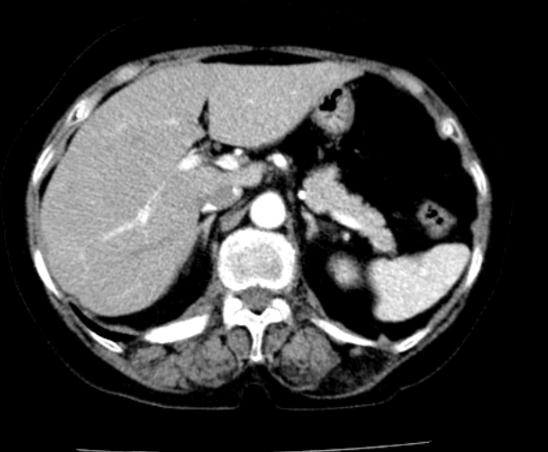

– Chụp cắt lớp vi tính ổ bụng: chưa phát hiện tổn thương thứ phát

Hình 2: Hình ảnh chụp cắt lớp vi tính ổ bụng |